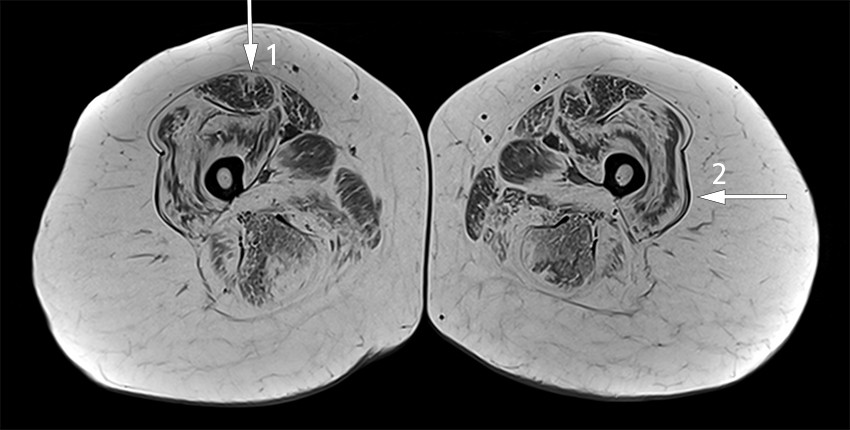

På bakgrunn av klinisk undersøkelse forenlig med myopati, positiv gentest og tidligere påvist fettinfiltrasjon på MR fant man ikke indikasjon for elektromyografi. Sykdomsbildet ble etter samtykke fra kvinnen diskutert anonymt i en nasjonal videokonferanse med kolleger fra hele landet som arbeider med sjeldne muskelsykdommer. Det ble anbefalt å gjøre MR-undersøkelse av alle muskler, og disse viste et karakteristisk mønster med fettinfiltrasjon hovedsakelig i proksimale muskler i over- og underekstremiteter (figur 1).

MR-undersøkelse benyttes i økende grad i utredning av sykdommer som affiserer muskulatur, først og fremst for å velge egnet biopsisted, men også som diagnostisk verktøy for å gjenkjenne utbredelse og mønstre av muskelødem og fettinfiltrasjon. Kollagen 6-relaterte myopatier som Bethlem-myopati har et distinkt, men ikke patognomonisk mønster med sentral fettinfiltrasjon i m. rectus femoris og perifer fettinfiltrasjon i m. vastus lateralis med relativ utsparing sentralt, som resulterer i «sandwich-tegnet» (12–14).